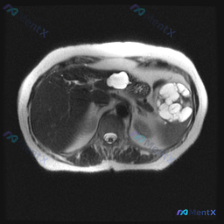

今天看到一份腹部MRI的T2WI图像,焦点在脾脏,整理一下读片的思考过程,避免踩坑。 先看核心影像表现 这是一张轴位T2WI,最突出的异常在脾脏: - 信号:脾实质内有数个类圆形极高信号影,信号强度接近脑脊液,提示是液体(浆液性为主)。 - 形态:边界清晰,但边缘呈分叶状,囊腔之间相互融合或紧邻,不...

整理了一份腹部囊性病变的影像资料,结合影像分析报告梳理下思路: 影像核心表现(T2加权轴位) - 肝脏:信号无明显弥漫或局灶异常 - 脾脏:可见类圆形多房性囊性病灶,边界清晰,T2呈显著高信号(符合囊液信号),无周围浸润或水肿带 - 上腹部额外发现:胰腺体尾部前方/胃后方,还有一个孤立的、边界清晰的...